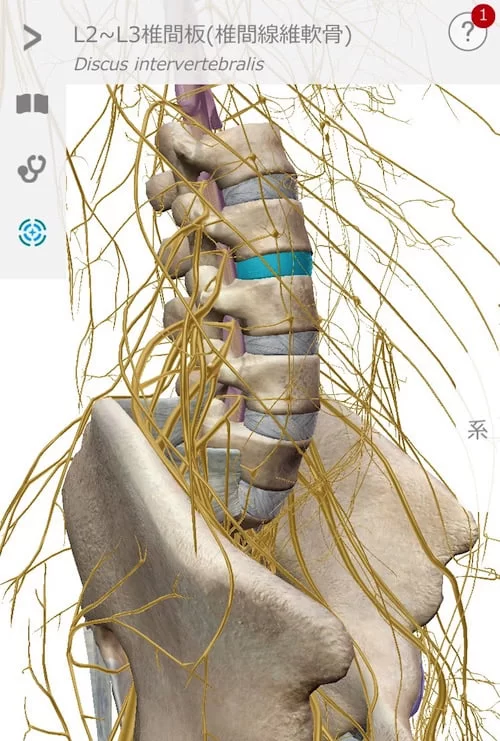

こんな感じで骨と骨の間に軟骨があります。

そして腰骨の周りには神経がいっぱい走っているのです。

そんな場所でこんな感じで軟骨が飛び出して神経に触れると

痛みやシビレが出る。それが一般的なヘルニアだと思って下さい。